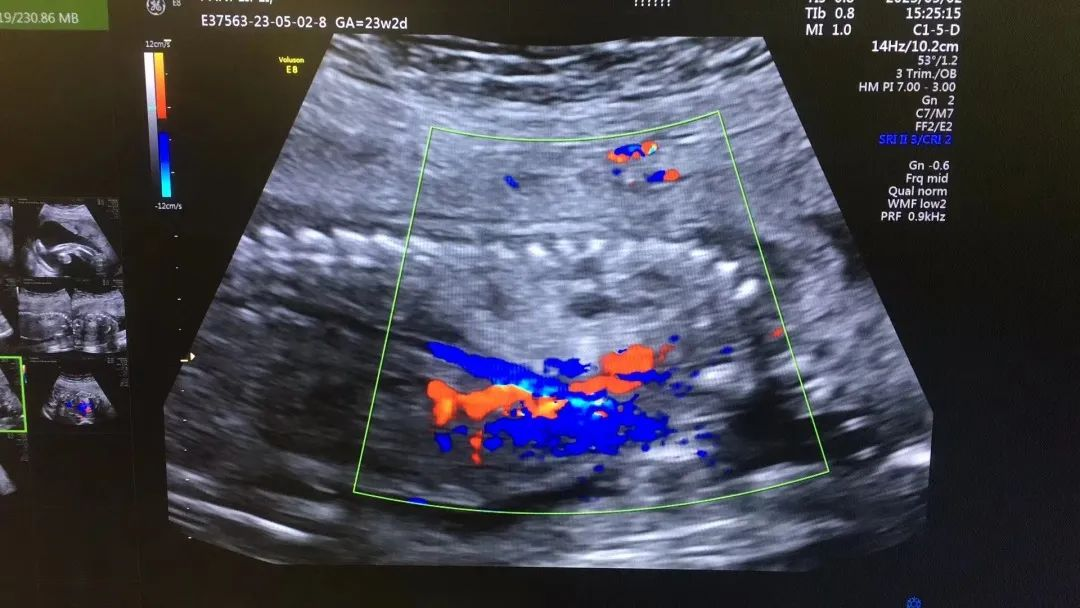

近日,我院超聲科醫(yī)生在給孕中期孕媽做四維彩超檢查時,發(fā)現(xiàn)胎兒查出異常,孕媽想留下這個寶寶,陷入了兩難。

武漢的劉女士(化名),前幾個月剛懷上寶寶,全家都特別高興。懷孕23周+時,劉女士在家人的陪伴下來到武漢仁愛醫(yī)院超聲科做了四維彩超檢查,當(dāng)醫(yī)生拿出檢查報告的時候,劉女士卻當(dāng)場傻眼了,原來,在四維彩超的報告里,診斷出了胎兒右肺囊性腺瘤樣病變,她的心頓時揪了起來!

劉女士看到檢查結(jié)果后,擔(dān)心該病變會影響腹中寶寶的健康,考慮是否應(yīng)該終止妊娠。隨即,武漢仁愛醫(yī)院超聲科王娟主任為劉女士耐心地解釋:“先天性肺囊腺瘤是一種肺組織錯構(gòu)畸形,先天性肺囊腺瘤畸形病例約70%的腫塊大小較穩(wěn)定;約20%腫塊產(chǎn)前明顯縮小或消失;僅10%腫塊是進(jìn)行性增大。單純的先天性肺囊腺瘤(CCAM)無水腫的胎兒可以密切隨訪,在28周前接受連續(xù)超聲復(fù)查,CVR<1.6,一般超聲動態(tài)監(jiān)測2~4周監(jiān)測一次,而對于CVR≥1.6的需要在28周前每周1-2次的超聲監(jiān)測,防止出現(xiàn)胎兒水腫,直到分娩。”